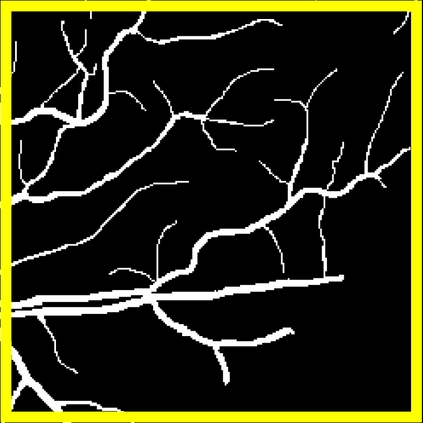

Blood vessel segmentation is crucial for many diagnostic and research applications. In recent years, CNN-based models have leaded to breakthroughs in the task of segmentation, however, such methods usually lose high-frequency information like object boundaries and subtle structures, which are vital to vessel segmentation. To tackle this issue, we propose Boundary Enhancement and Feature Denoising (BEFD) module to facilitate the network ability of extracting boundary information in semantic segmentation, which can be integrated into arbitrary encoder-decoder architecture in an end-to-end way. By introducing Sobel edge detector, the network is able to acquire additional edge prior, thus enhancing boundary in an unsupervised manner for medical image segmentation. In addition, we also utilize a denoising block to reduce the noise hidden in the low-level features. Experimental results on retinal vessel dataset and angiocarpy dataset demonstrate the superior performance of the new BEFD module.